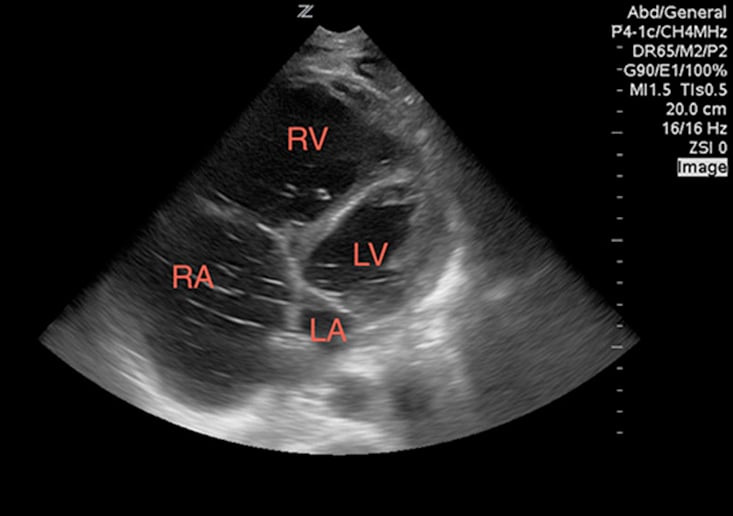

While viewing the cardiac windows, gain a sense of the overall cardiac function and ejection fraction (EF). Emergency sonographers can categorize cardiac contractility as normal, depressed, or severely depressed and can identify a severely depressed left ventricular EF with nearly 100% sensitivity.9 In a heart with a normal EF, the anterior leaflet of the mitral valve will touch, or nearly touch, the inter-ventricular septum. You may choose to measure the distance during diastole from the anterior leaflet of the mitral valve to the inter-ventricular septum using M-mode. A distance of less than 7 mm suggests a normal EF, whereas greater than 7mm is 100% sensitive for a severely depressed EF (Image 2). This is known as E-point septal separation, or EPSS.10 In the apical four-chamber view, compare the diameters of the right (RV) and left ventricle (LV). A normal RV is less than two-thirds the size of the LV. A dilated RV in the correct setting is 98% specific for right heart strain from a pulmonary embolism11 (Image 3). You may also note a wall motion abnormality as evidence of an old or new myocardial infarction. Adding color to the exam in Doppler mode enables you to also identify valve incompetence.